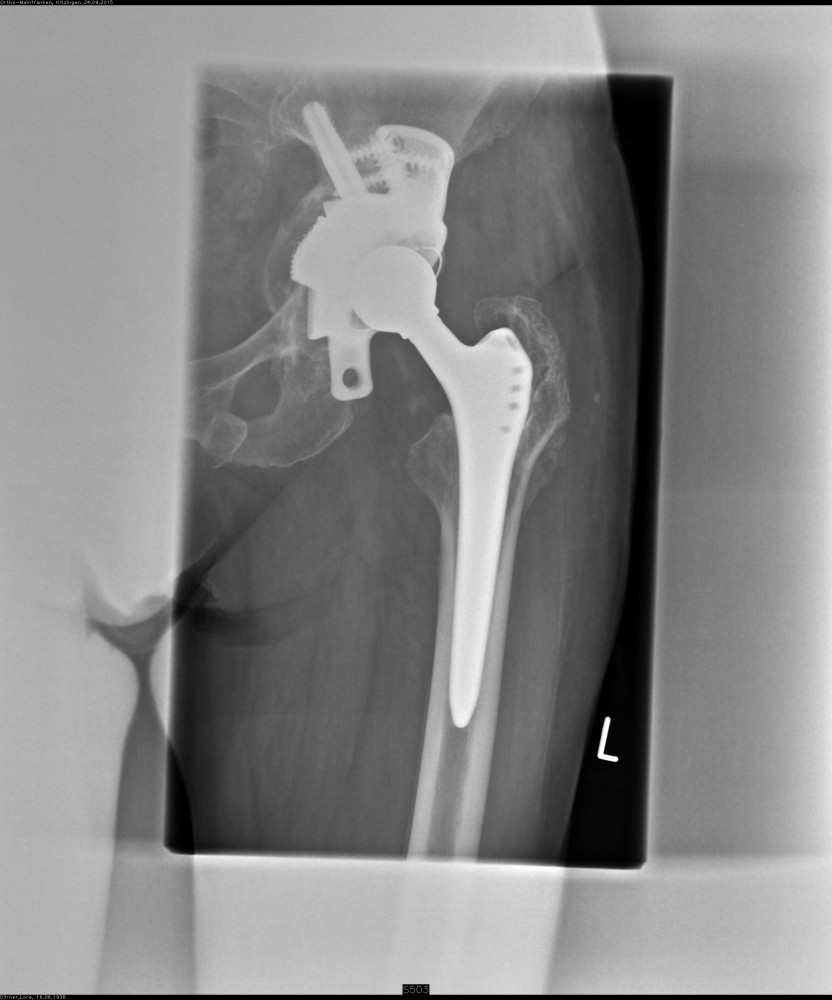

Wechsel einer Hüftgelenkpfanne

Im Falle einer Pfannenlockerung mit wenig Knochendefekt ist es möglich das vorhandene Implantat in ein größeres Implantat zu wechseln. Bei größeren Knochendefekten wird der Austausch mit Hilfe eines modular aufgebauten Pfannenrevisionssystems durchgeführt.

Bei sehr großen Knochendefekten im Beckenbereich kann ein individueller Beckenteilersatz geplant werden. Hierzu wird im Vorfeld eine dreidimensionale Computertomographie des Hüftgelenkes zur exakten Darstellung der knöchernen Verhältnisse angefertigt. Im Rahmen der Planung erfolgt eine präzise Anpassung des Implantates an die individuellen knöchernen Gegebenheiten unter Berücksichtigung von Beinlänge und Drehzentrum.

Aufgrund des hohen planerischen Aufwandes ist jedoch bis zur Operation eine längere Vorlaufzeit notwendig.